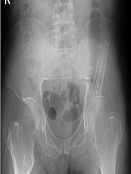

Kıkırdak hücresi üreten kötü huylu bir tümördür. En sık 30-60 yaş arasında görülür. Sıklıkla femurun (uyluk kemiği) her iki ucunda, humerusun (kol kemiği) üst ucunda, pelvis (leğen kemiği), kaburga, omurga ve kafa kemiklerinde görülebilir. Kondrosarkomlar primer ve sekonder olmak üzere iki gruba ayrılır. Elde nadir görülmesine karşın malign el tümörleri içerisinde üst sıradadır.

1. Klasik Medüller Kondrosarkom

Sıklıkla pelvis (leğen kemiği), femurun (uyluk kemiği) ve humerusun (kol kemiğinin) üst ucunu tutar. Kondrosarkomların %80’nini oluşturur. 30 yaş üzerinde sık görülür. Grade I kondrosarkomlarda lezyon içerisine girilerek geniş küretaj yapılır. Grade II ve üzeri lezyonlarda lezyon için cerrahi girişimlerde lokal nüks riski çok yüksektir. Bu tip kondrosarkomlarda mutlaka geniş sınırlar ile rezeksiyon yapılmalıdır. Histolojik derece çok yüksek ise kemoterapi eklenebilir.

Grafide sakrumda orta hat yerleşimli, belirsiz sınırlı, litik bir kitle görülür. Düz grafide görüntü almak çok zordur. MRI incelemesi, tümörün tüm uzanımını, öndeki rektum, mesane, damarlar ve özellikle sinir kökleri ile ilişkisini gösterir. BT’de kemikteki destrüksiyon en iyi şekilde görülür. Ayırıcı tanıda dev hücreli tümör, anevrizmal kemik kisti, kondrosarkom dikkate alınmalıdır.